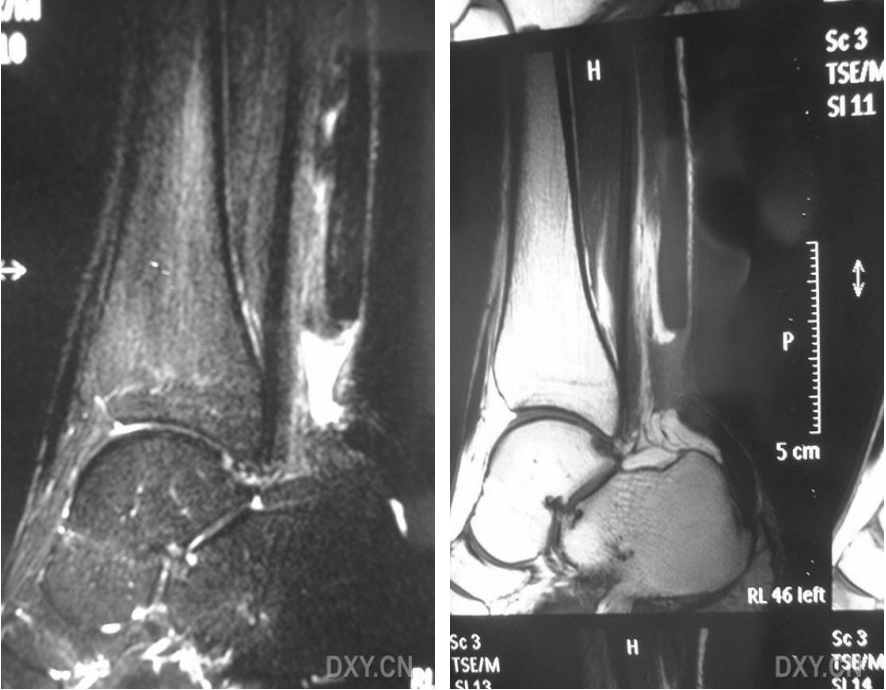

5.2MRI检查

完全撕裂:T1WI、T2WI示跟腱增粗,信号均匀或不均匀增高,腱束分离不连续。

部分撕裂:局部信号增高,可见部分连续腱束影,周围软组织水肿。

MRI可精准判断断裂部位、范围及合并损伤(如腱周炎、骨髓水肿),为手术方案制定提供依据。